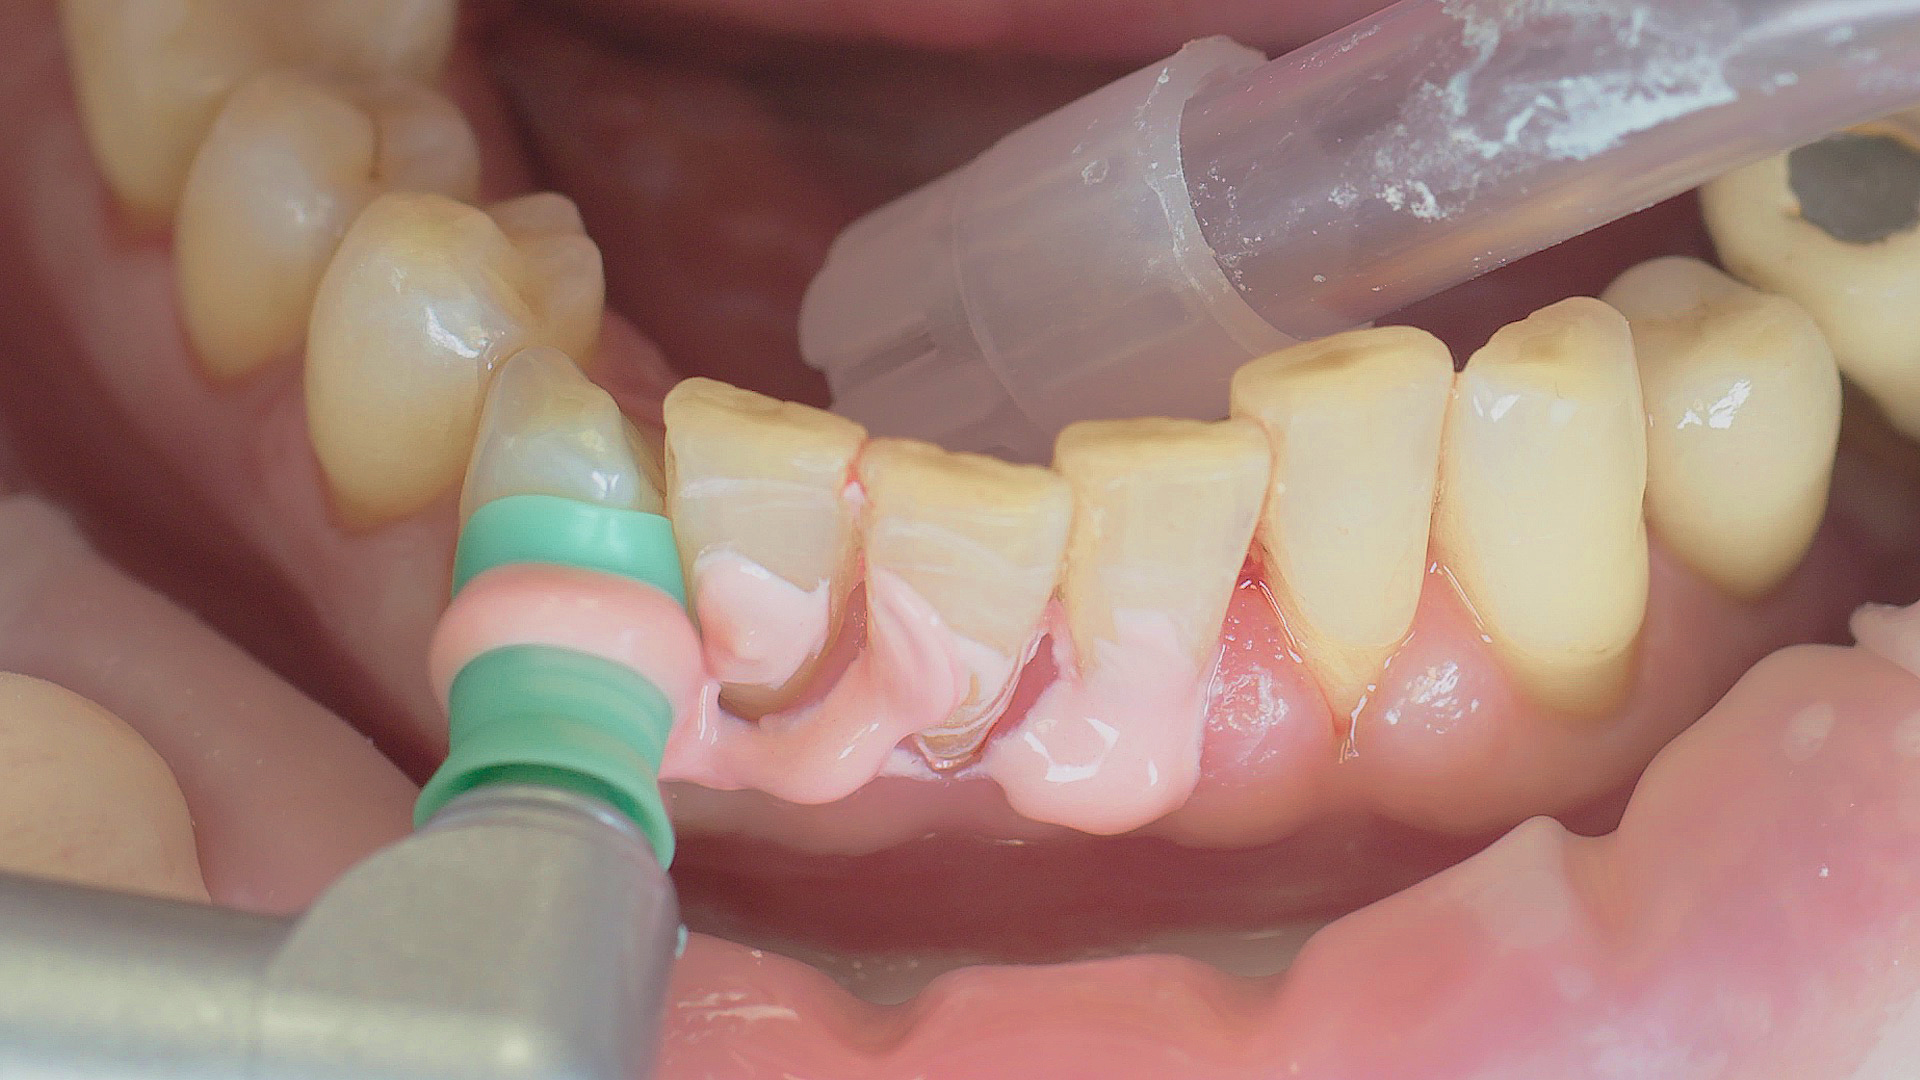

Healthy peri-implant tissue does not show any signs of redness, swelling or bleeding, neither does it secrete pus when probed.[5] Based on the consensus document, Prof. Giovanni Salvi explained the importance of regu- lar probing — preferably with a flexible probe, as implant components often tend to obstruct the procedure.[5] In the case of mucositis or initial peri-implantitis already being present, the non-surgical removal of hard deposits and biofilm should be attempted first. For this purpose, ultra- sonic power and special instruments designed to protect the implant should be employed (Fig. 3; piezo scaler Tigon+ with 1I, W&H). In case of no remission, the recall frequency needs to be increased. However, specific recommendations, applicable to individual cases, are not yet available in this context.[15]